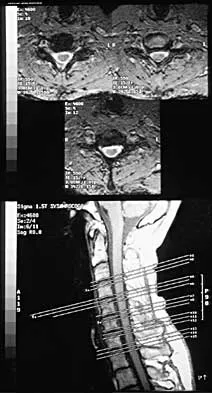

Question 62

An Asian 45-year-old man has bilateral upper extremity dysfunction. Figure 35a shows a T2-weighted sagittal MRI scan of the cervical spine, and Figure 35b shows a T2-weighted axial MRI scan at the level of the C3 vertebral body. What is the most likely pathologic process?

Explanation